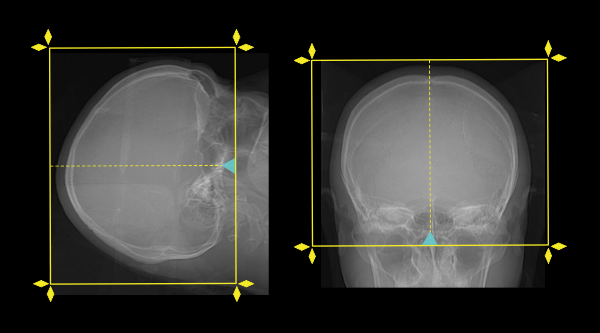

- Plan the scan starting point (laser indicator) at the upper lip of the patient.

- Plan the scan range from the skull vertex to skull base.